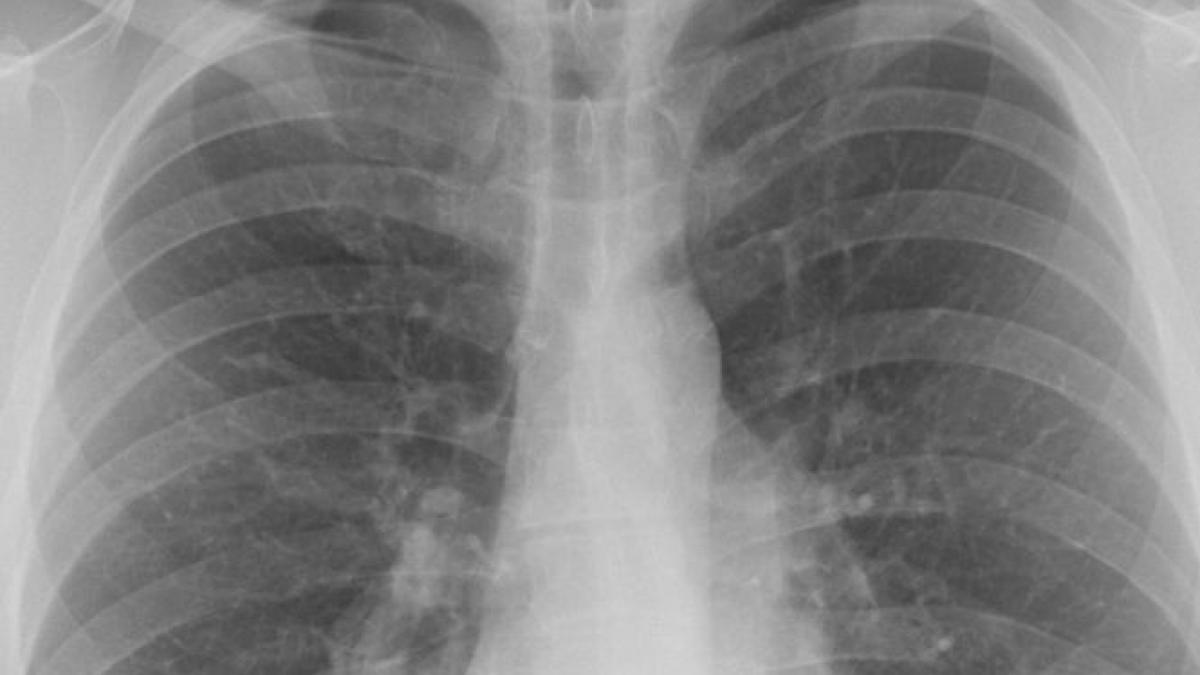

Cum arătau plămânii femeii din Alba care a murit de Covid-19, deși nu avea nicio altă boală. FOTO27 Iun

O femeie de 39 de ani din Alba Iulia a murit de COVID-19. Medic: „Nu mai avea suprafață pulmonară cu care să respire”24 Iun